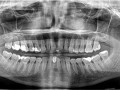

Rozległa torbiel zawiązkowa żuchwy

Paulina Adamska, Maria Mikołajska, Anna Janowska, Anna Starzyńska